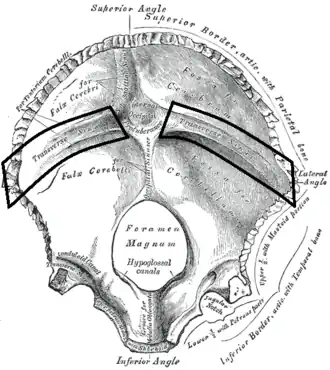

Groove for transverse sinus

| Groove for transverse sinus | |

|---|---|

Human skull (parietal bones removed). Position of groove for transverse sinus shown in red. | |

Interior surface of occipital bone. (Groove for transverse sinus runs laterally on either side of the internal occipital protuberance.) | |

The groove for transverse sinus is a groove which runs along the internal surface of the occipital bone, running laterally between the superior and inferior fossae of the cruciform eminence. The transverse sinuses travel along this groove.